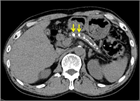

1. 膵管内の結石(膵石)を認めた場合と、膵全体に分布する複数かつびまん性の石灰化を認めた場合は慢性膵炎と診断できる(推奨度1)

1. 加齢現象に伴い膵石が観察される場合がある。

1. 石灰化を伴った膵腫瘍がまれに存在する。